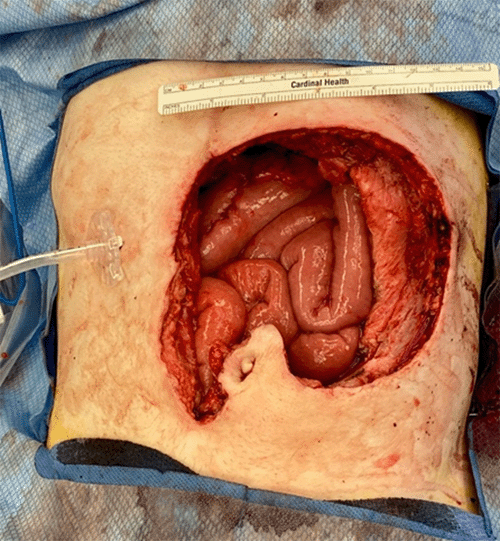

A 35-year-old male with a history of alpha-thalassemia x-linked intellectual disability (ATRX), failure to thrive, and dependent on gastrostomy tube feeding since one year of age presented with a fungating mass surrounding his gastrostomy tube. Due to the coronavirus pandemic, evaluation of the lesion was delayed until the following year. On initial evaluation, the exophytic mass was found to be approximately 5 × 6 cm circumferentially surrounding the gastrostomy tube, and punch biopsy confirmed moderately differentiated squamous cell carcinoma (SCC). CT scan of the abdomen and pelvis demonstrated 3.7 × 3.1 cm soft tissue density in the left anterior abdominal wall surrounding the gastrostomy tube as well as 2.1 × 3.2 cm soft tissue density in the stomach adjacent to the feeding tube, which appeared to represent an extension of the cutaneous malignancy. There was no radiographic evidence of metastatic disease. The patient underwent upper endoscopy revealing an intraluminal, ulcerated mass circumferentially surrounding the gastrostomy tube and appearing to grow in from the outside (Figure 1). Endoscopic biopsies demonstrated invasive, focally keratinizing, moderately differentiated SCC.

Figure 1. Endoscopic Images of Intraluminal Mass. Published with Permission